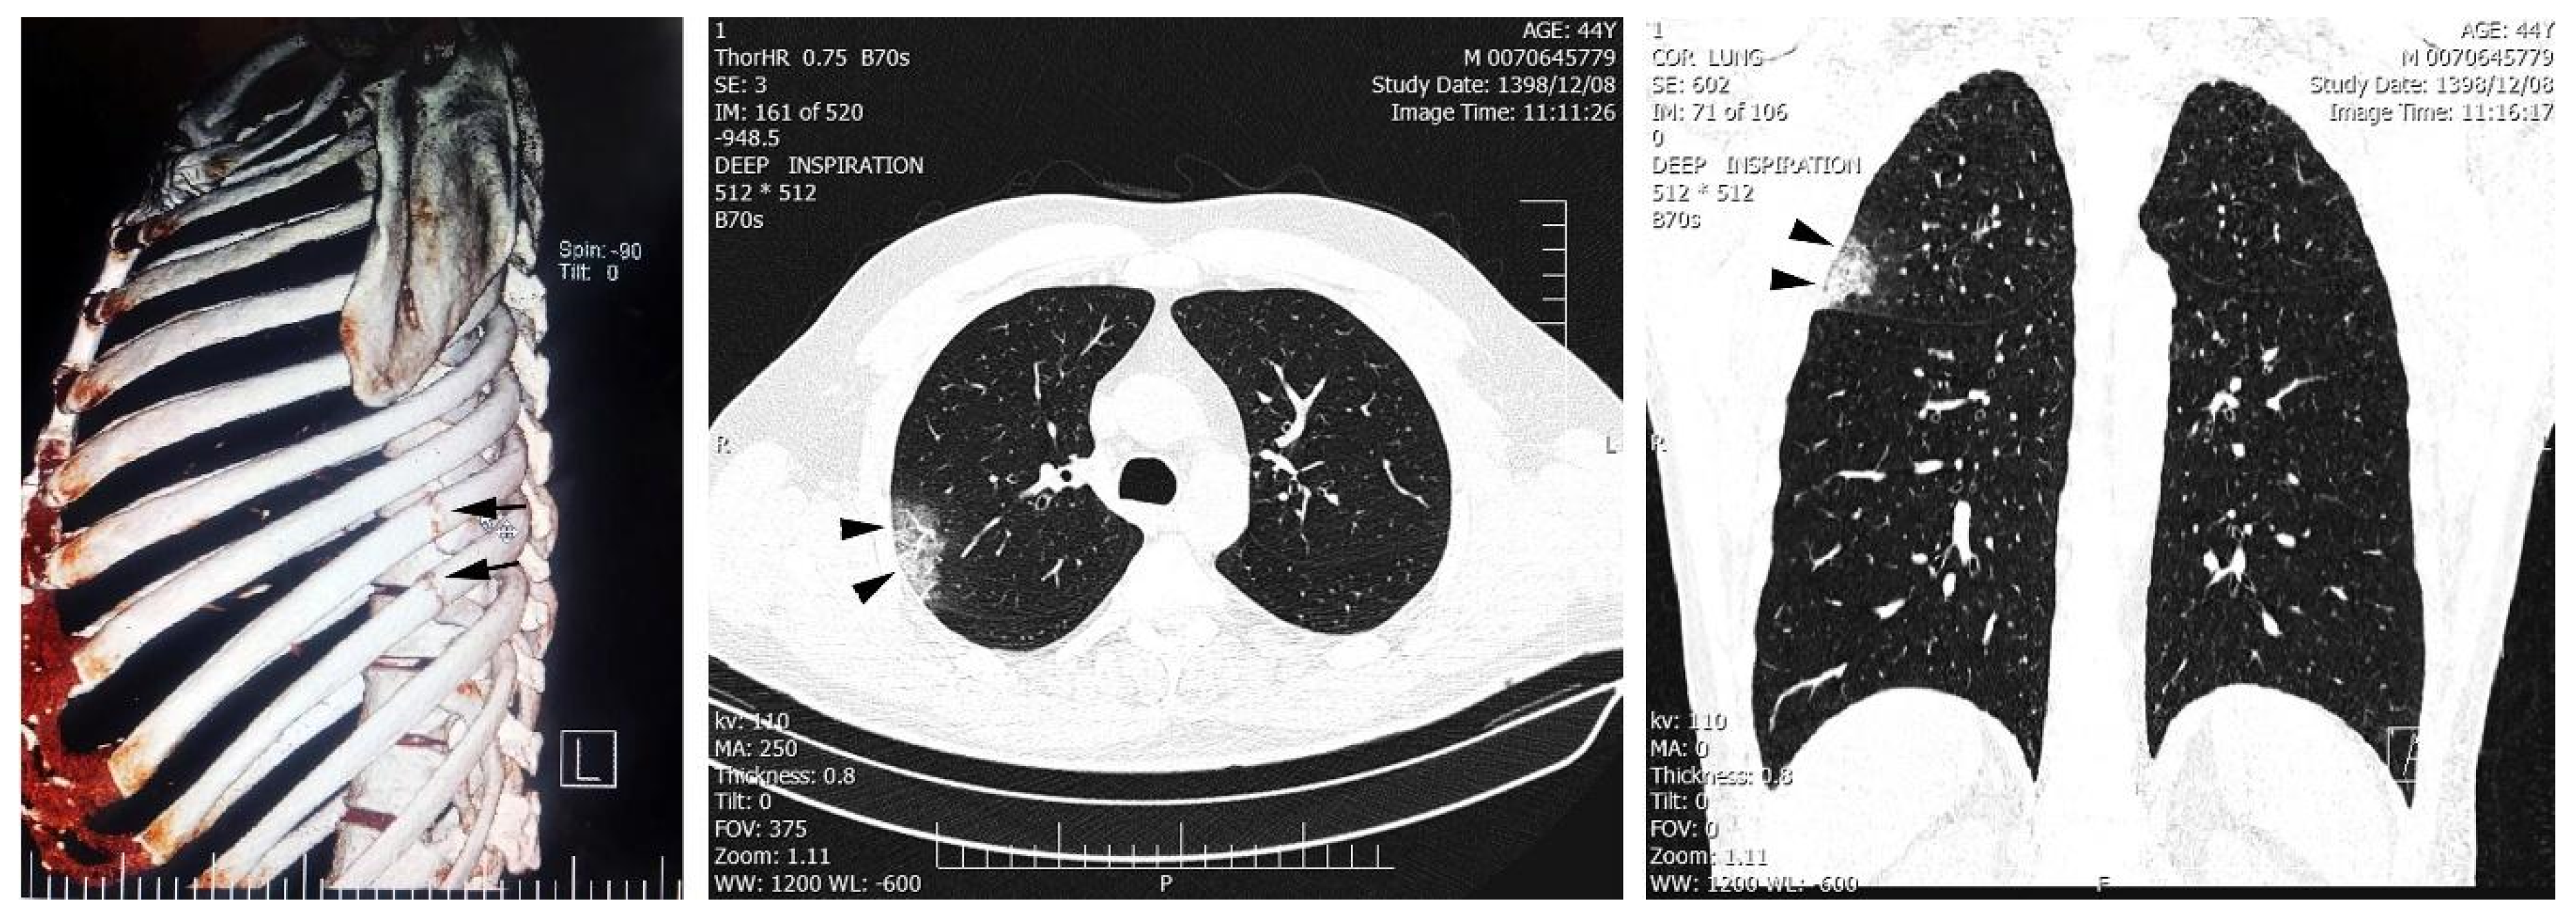

A chest CT scan was performed (Figure 1), which revealed left 8th and 9th ribs fracture along with an ill-defined patchy ground-glass opacity in the upper lobe of the right lung. Due to high suspicion of SARS-CoV-2 infection, an upper respiratory tract swab for severe acute respiratory syndrome coronavirus-2 (SARS-CoV-2) was obtained, and a positive real-time reverse-transcriptase polymerase chain reaction (rRT-PCR) assay confirmed the diagnosis of COVID-19 infection.

Figure 1. Fractures are seen in the left 8th and 9th ribs (arrow). Peripheral patchy ground-glass opacity in the right upper lobe is observed due to viral pneumonia (arrowheads). Neither pleural effusion nor lymphadenopathy were found. Written informed consent was obtained from the patient for publication of this case report.